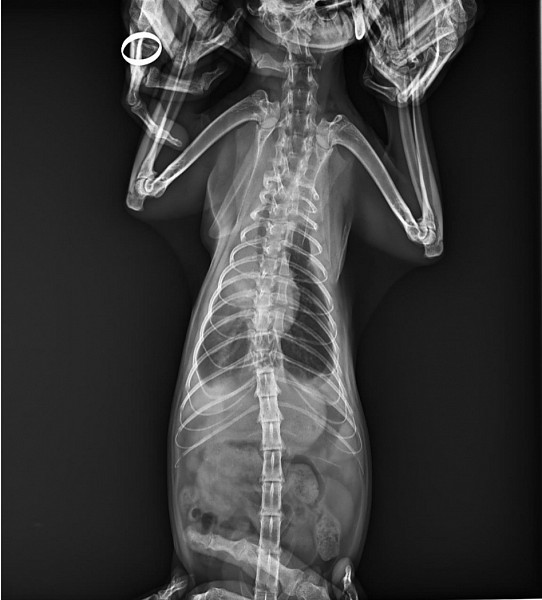

Верошпирон используют с осторожностью у мелких животных, больных почечной недостаточностью или патологии водно-электролитного баланса . Особая осторожность при применении у собак и кошек с болезнью Аддисона, почечной недостаточностью, гиперкалиемией . У кошек в качестве побочного действия на спиронолактон развивается сильный зуд в области морды .